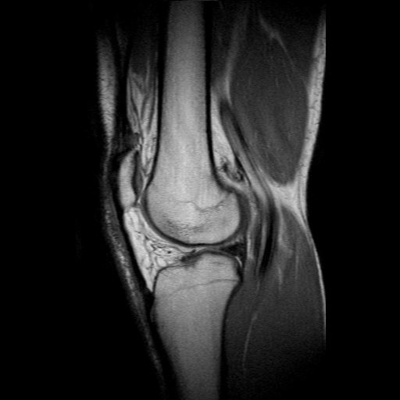

-les liquides: le liquide céphalo rachidien sur une coupe du cerveau (=liquide qui baigne le cerveau, donc en gros c'est la couleur du cerveau quoi), le liquide synovial dans une articulation...

Si ils sont en hypersignal, on s'orientera vers une pondération rho ou T1